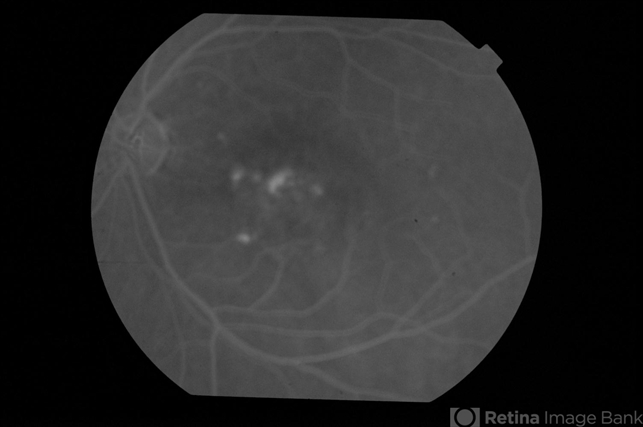

- CSCR subfoveal leak

- 52-year-old male with left eye CSCR of 6 months duration. Mid-phase fluorescein angiogram shows multiple leaks including a sub-foveal one. He was treated with PDT with complete resolution of fluid.